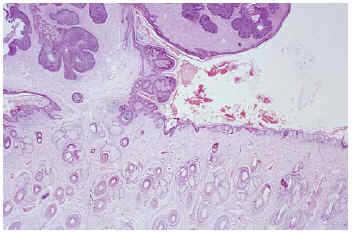

Fig. 1.--Nevo sebáceo asociado a carcinoma basocelular (izquierda) y verruga vírica (derecha) en un paciente de 27 años.

De los 366 casos estudiados, 207 eran varones y 159 mujeres. La edad media en el momento del diagnóstico fue de 38 años (límites, 2-85) y las localizaciones más frecuentes, el cuero cabelludo (239; 65,3 %), la región frontal (76; 20,7 %) y la cara (36; 9,8 %). Se extirparon 28 en menores de 16 años. El tamaño oscilaba entre 0,5 y 2,5 cm (1,3 cm de tamaño medio). En 37 pacientes (10,1 %) el nevo sebáceo era asiento de otras entidades histológicas (fig. 1-5).

Las cuatro entidades histológicas más frecuentemente relacionadas con el nevo fueron la verruga vírica en 15 pacientes (4,09 %), siringocistadenoma papilífero en 12 pacientes (3,27 %), tricoblastoma en 8 pacientes (2,18 %) y carcinoma basocelular en 7 pacientes (1,91 %). En 12 casos se observaron lesiones múltiples que se desarrollaban sobre un mismo nevo. Se identificaron hasta tres lesiones diferentes asociadas simultáneamente al nevo sebáceo (tabla 1). La mayoría de las lesiones asociadas se localizaron en el cuero cabelludo (60,52 %), región frontal (21,05 %) y cara (13,15 %). El tipo histológico y la distribución de las lesiones asociadas según edad se reflejan en tablas 2 y 3.